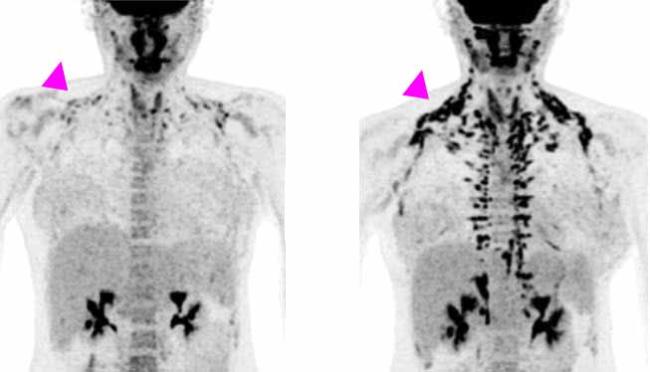

But there’s another kind of fat, called brown fat. Its job is to help maintain body temperature by burning triglycerides to generate heat. Until about 15 years ago, humans were believed to lose most of their brown fat after infancy. It was thought that any brown fat that remained in adults didn’t serve any function. Since then, researchers have learned that nearly every adult human has some functioning brown fat. It’s found only in certain places in people: the neck and shoulders, along the spine, and around the kidneys.

Brown fat may have a big impact on our metabolic health. In mice, activating brown fat reduces levels of triglycerides and cholesterol in the blood. It also prevents atherosclerosis, a sticky buildup along the artery walls that contributes to heart disease. In people, more brown fat is associated with lower rates of type 2 diabetes, cardiovascular disease, high blood pressure, and heart failure. So, having more brown fat, or more active brown fat, may be good for metabolic health. This suggests that increasing brown fat activity might protect against metabolic syndrome.